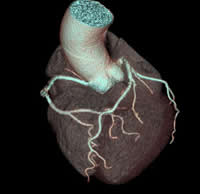

検査は、ベッドに寝ているだけで終了します。また、当院検査は、一回の撮影で同時に複数の輪切り像が得られる最新型ボリュームCTスキャナです。 得られた輪切り画像から下のような精密な立体像を作ることも可能です。

心臓3次元画像